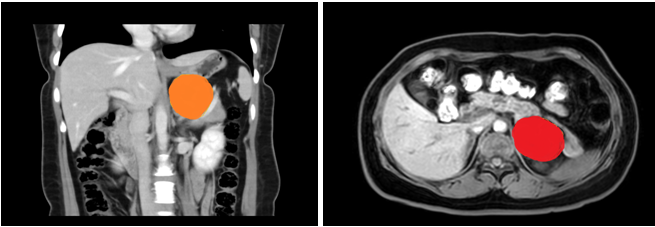

患者,女性,35岁,在六合彩网站 上腹部CT增强示:左侧腹膜后囊性病变,支气管囊肿不除外;入院后上腹部MRI平扫+DWI+增强扫描+MRCP示:左侧肾上腺上方囊性病变,考虑来源腹膜后间隙,1)支气管源性囊肿2)淋巴管囊肿可能,建议复查。

在张煜副主任带领下,经过肝胆外科全科细致讨论,认为占位较大,位置靠后,微创难度大,需完善相关检查,精细术前准备。经过医护一体化管理,打消了患者的术前顾虑,在全麻下行腹腔镜下腹膜后囊性占位手术+广泛腹腔粘连松解术,手术顺利,术后病理结果为良性,患者术后一周内顺利出院。患者表示,术后经过了解,得知此例手术难度较大,目前恢复良好,特意送来锦旗表达感谢。